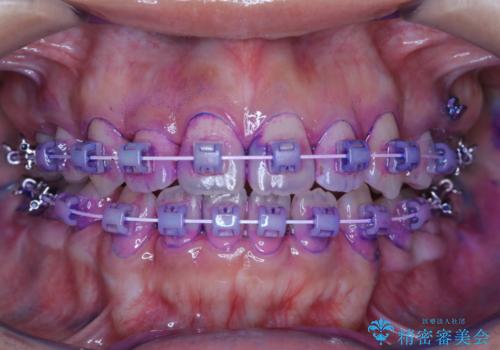

ワイヤー矯正中のクリーニング

- ワイヤー矯正中に、磨ききれないところがあるのと、口臭が気になるとのことでした。

そのためPMTC30分コースを行いました。

ワイヤー矯正中は、装置の周りに汚れが付きやすく虫歯や歯周病のリスクが高まります。そのため、ワイヤー調整の診察の際、一緒にクリーニングを行うことで、虫歯・歯周病・口臭予防になります。歯ブラシだけでは取り除くことが難しい細かい部分などに、専門的な機械や機材を使用して定期的なケアを行うことをおすすめしています。